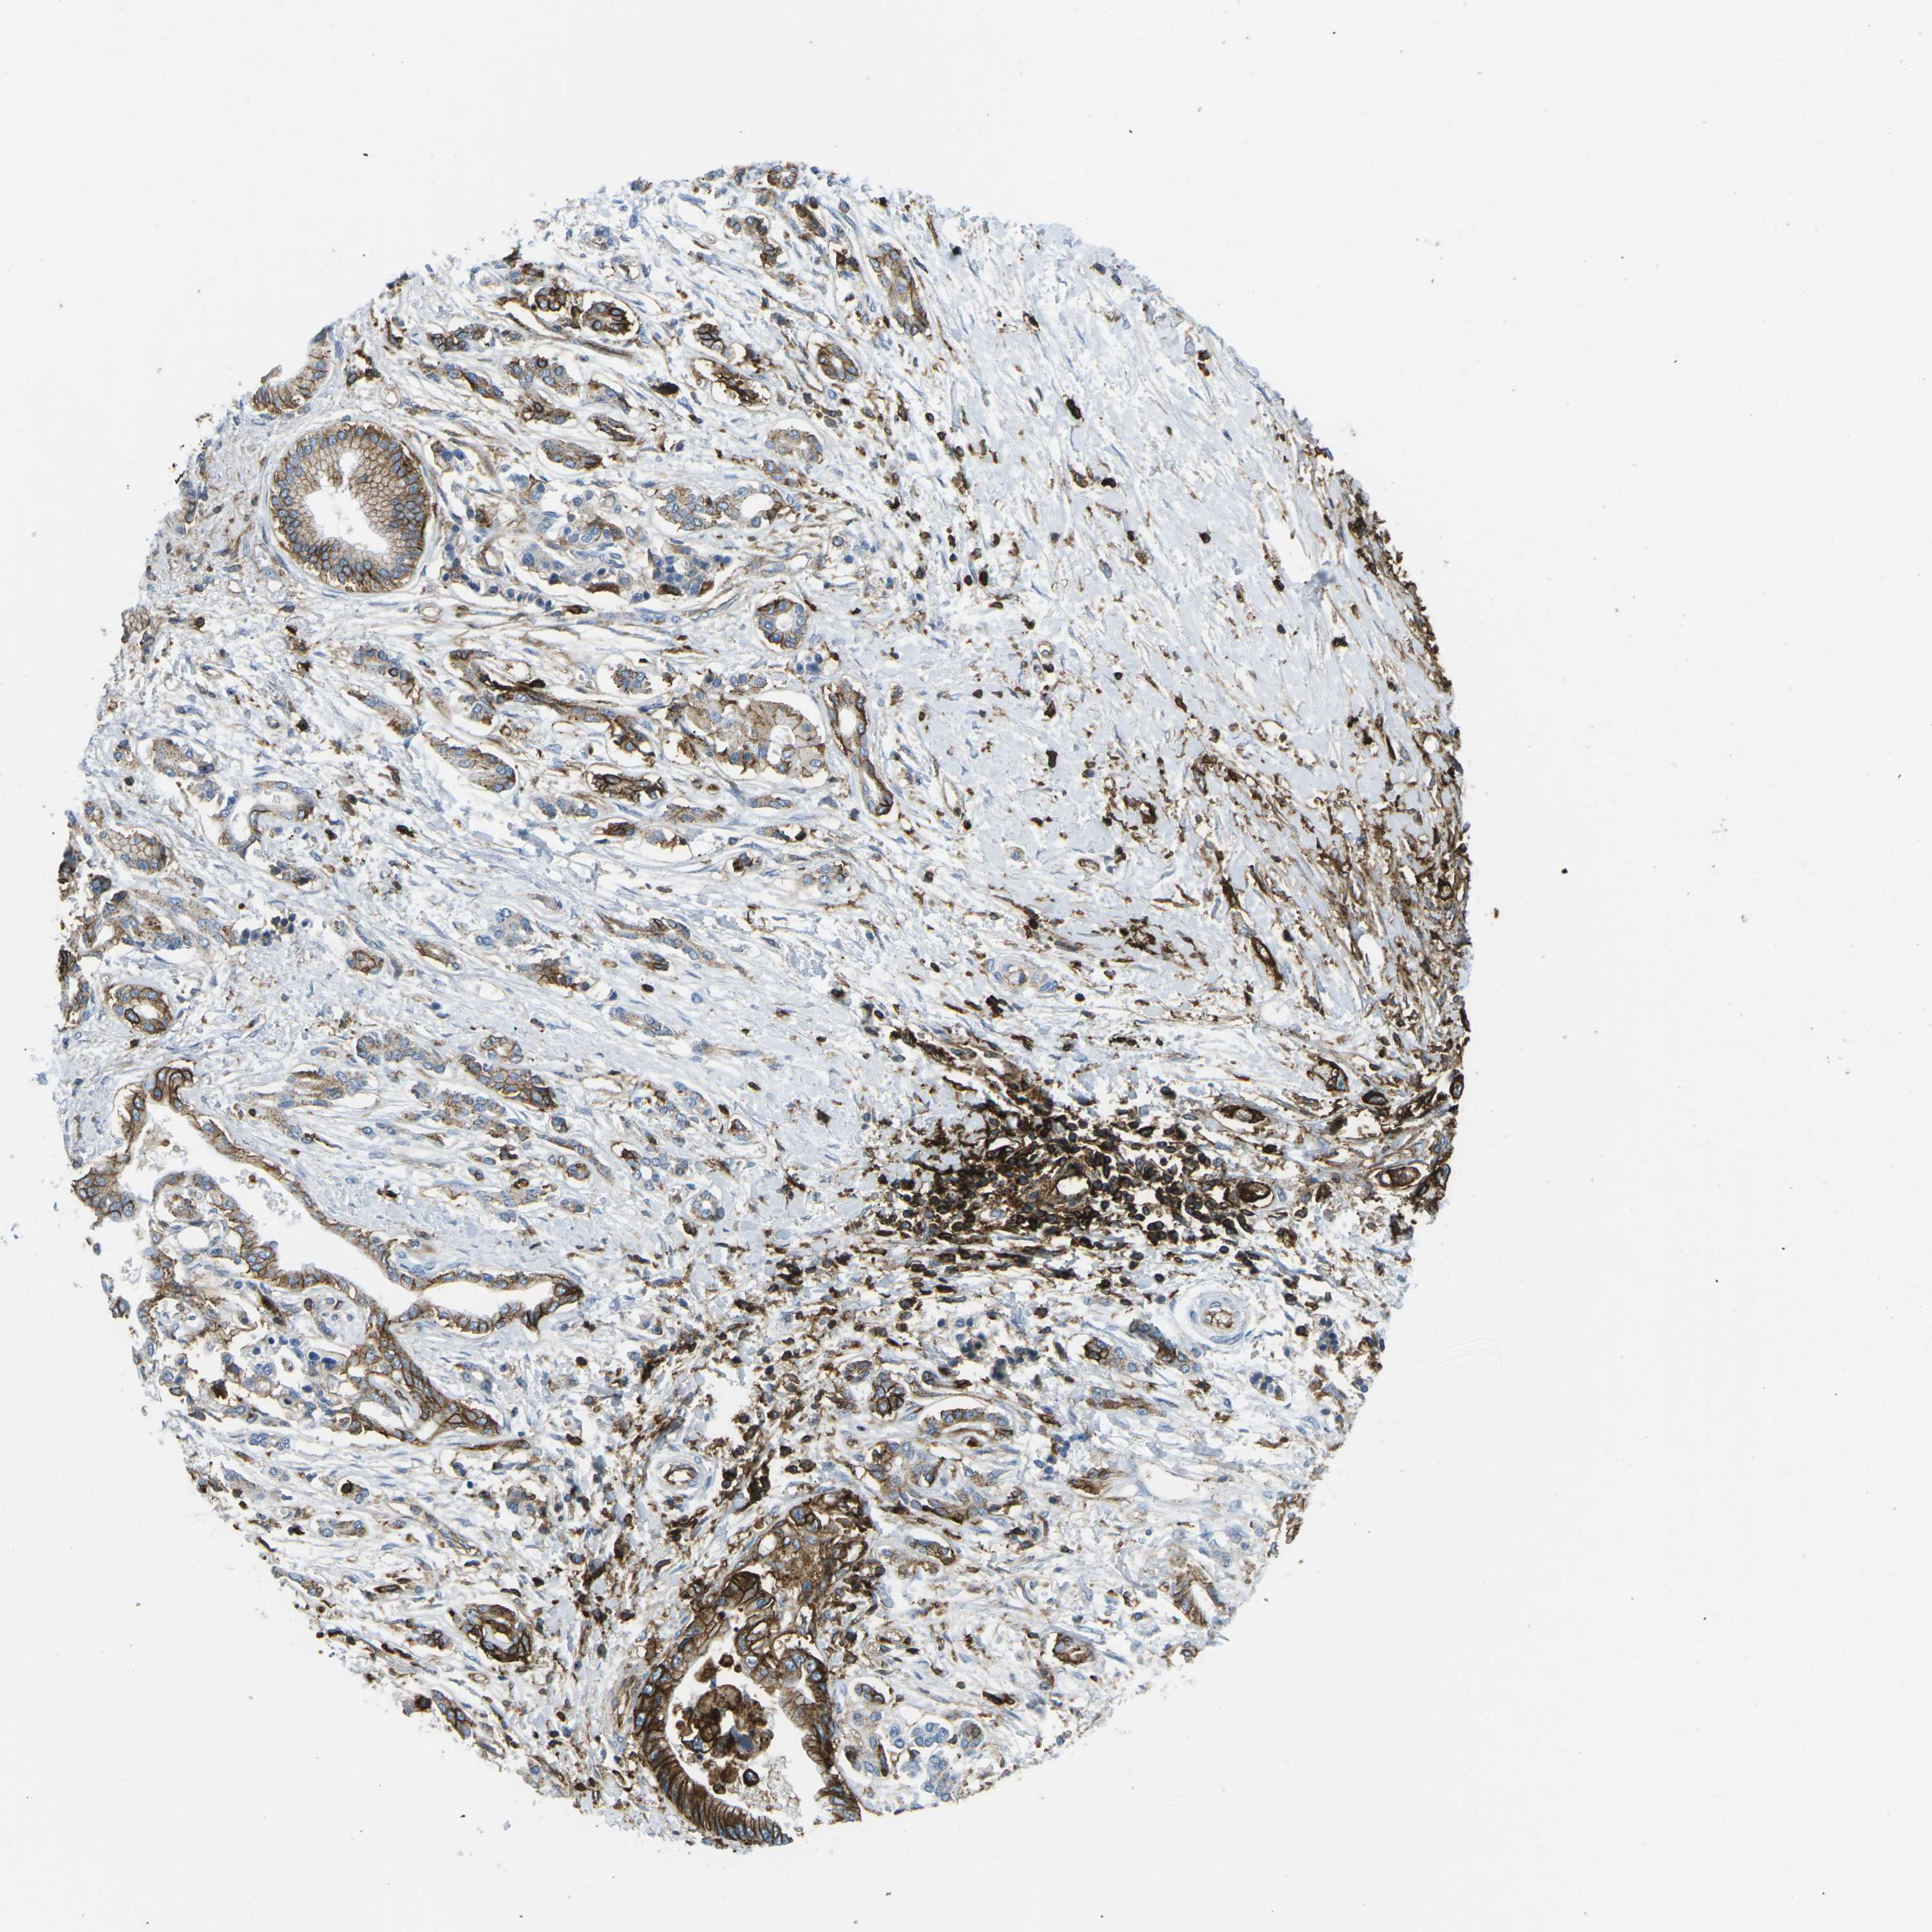

PANCREATIC CANCER - Protein expressioni

A mouse-over function shows sample information and annotation data. Click on an image to view it in a full screen mode. Samples can be filtered based on level of antibody staining by selecting one or several of the following categories: high, medium, low and not detected. The assay and annotation is described here.

Note that samples used for immunohistochemistry by the Human Protein Atlas do not correspond to samples in the TCGA dataset.

Antibody stainingi

Antibody staining in the annotated cell types in the current human tissue is reported as not detected, low, medium, or high, based on conventional immunohistochemistry profiling in selected tissues. This score is based on the combination of the staining intensity and fraction of stained cells.

Each image is clickable and will lead to virtual microscopy that enables deeper exploration of all samples and also displays staining intensity scores, fraction scores and subcellular localization as well as patient and tissue information for each sample.

Antibody CAB015418

Staining

High

Medium

Low

Not detected

Intensity

Strong

Moderate

Weak

Negative

Quantity

>75%

75%-25%

<25%

None

Location

Nuclear

Cytoplasmic/membranous

Cytoplasmic/membranous,nuclear

Adenocarcinoma, NOS